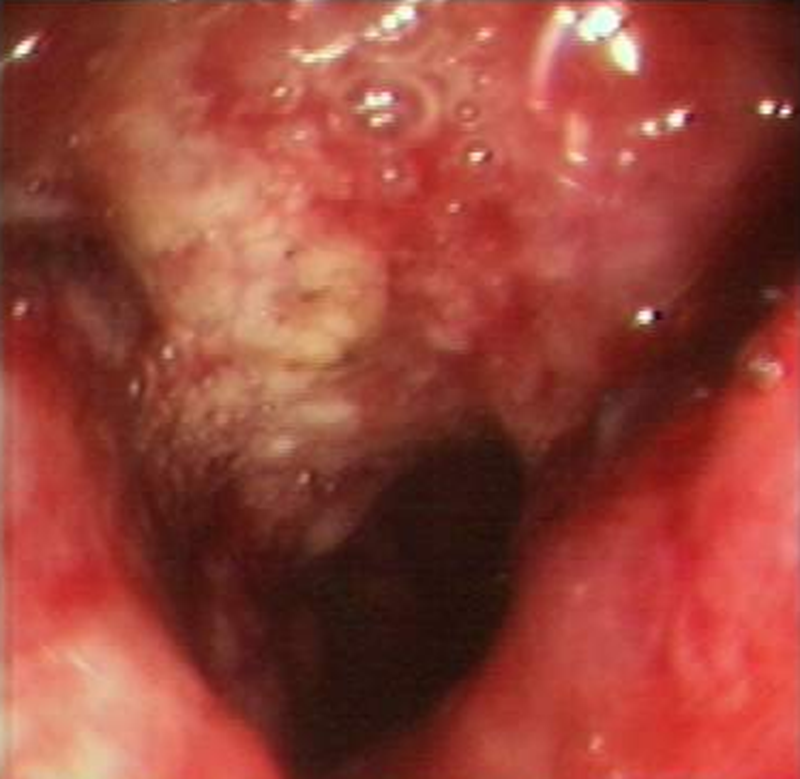

肠镜下直肠肿瘤

肠癌隆起型

直肠癌浸润型

肠癌溃疡型